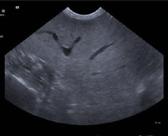

Ecografia addominale

• Lieve nefromegalia e nefropatia bilaterale;

• splenomegalia e splenopatia diffusa.

Reni: lievemente aumentati di dimensioni, con diffusa iperecogenicità parenchimale e lieve riduzione della normale distinzione cortico-midollare.

Milza: aumentata di dimensioni, con margini arrotondati e parenchima diffusamente disomogeneo.

• Nefromegalia e nefropatia bilaterale;

• epatomegalia ed epatopatia diffusa;

• splenomegalia e splenopatia diffusa. DESTRO

Reni: aumentati di dimensioni, con diffusa iperecogenicità parenchimale e pelvi lievemente distesa da contenuto anecogeno.

Fegato: aumentato di dimensioni con margini arrotondati, parenchima diffusamente iperecogeno a trama fine in assenza di lesioni focali.

Milza: moderatamente aumentata di dimensioni, con parenchima nei limiti per ecostruttura ed ecogenicità.